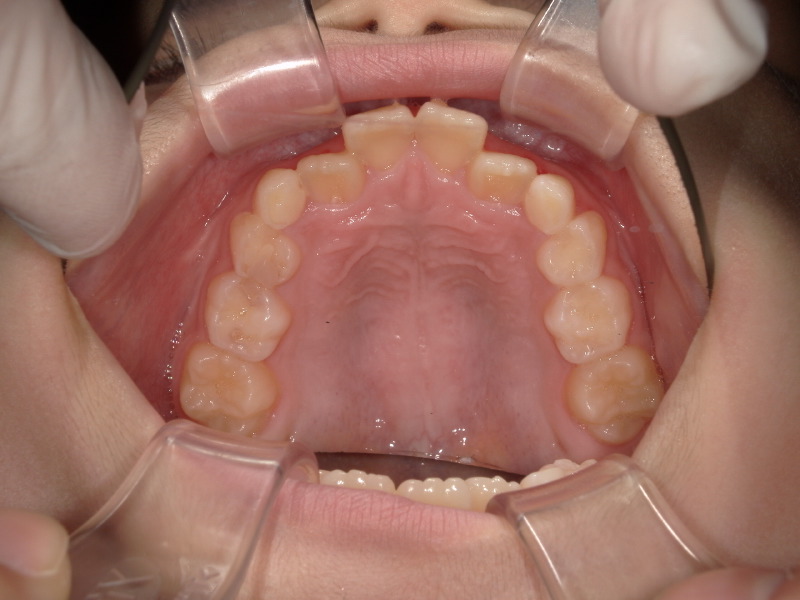

上の歯並びの変化

こちらも3ヶ月の経過です。

がたつきがかなり改善しています。

この頃はまだアクティビティーとマウスピースの装着のみです。